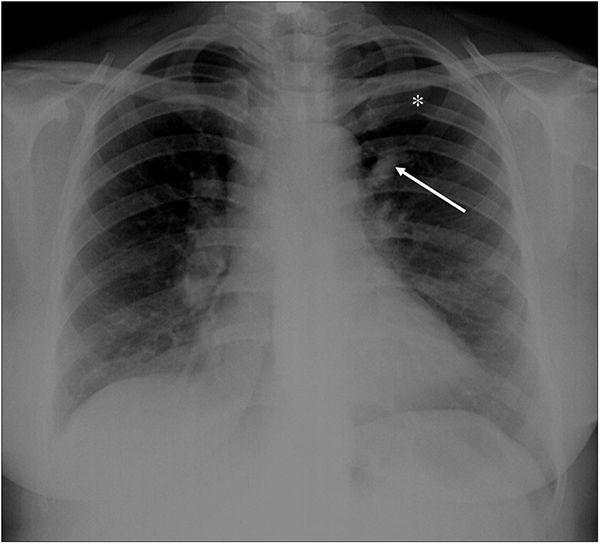

A 22-year-old woman was referred to our emergency radiology unit with sudden onset of shortness of breath and left-sided chest pain. The chest radiography revealed left hilar tubular opacite (arrow) and hyperaeration (asterisk) in the upper zone of the left lung (Fig. 1). The contrast enhanced computed tomography (CT) showed a non-contrast enhancing tubular mass that was seen extending from the left hilum, with surrounding hypoattenuation of the apicoposterior segment of the left upper lobe (asterisk), a finding indicative of hyperinflation (Fig. 2A). There was also no connection between the non-contrast tubular mass (arrows) and pulmonary artery of the apicoposterior segment in the left upper lobe (Fig. 2B–C). CT findings were also including mucocele and occlusion of the bronchus central to the mucocele. CT results (mucocele with hyperaeration of the adjacent lung parenchyma) were considered pathognomonic for bronchial atresia. Surgical treatment was no performed because the patient refused operation.

Radiologically, bronchial atresia is associated with a triad of findings: focal interruption of a bronchus; associated distal mucus impaction (bronchocele) that is visible as a branching tubular or ovoid area of increased attenuation; and associated hyperinflation of the obstructed pulmonary segment.2 Bronchial atresia should be kept in mind in patients with shortness of breath and chest pain.